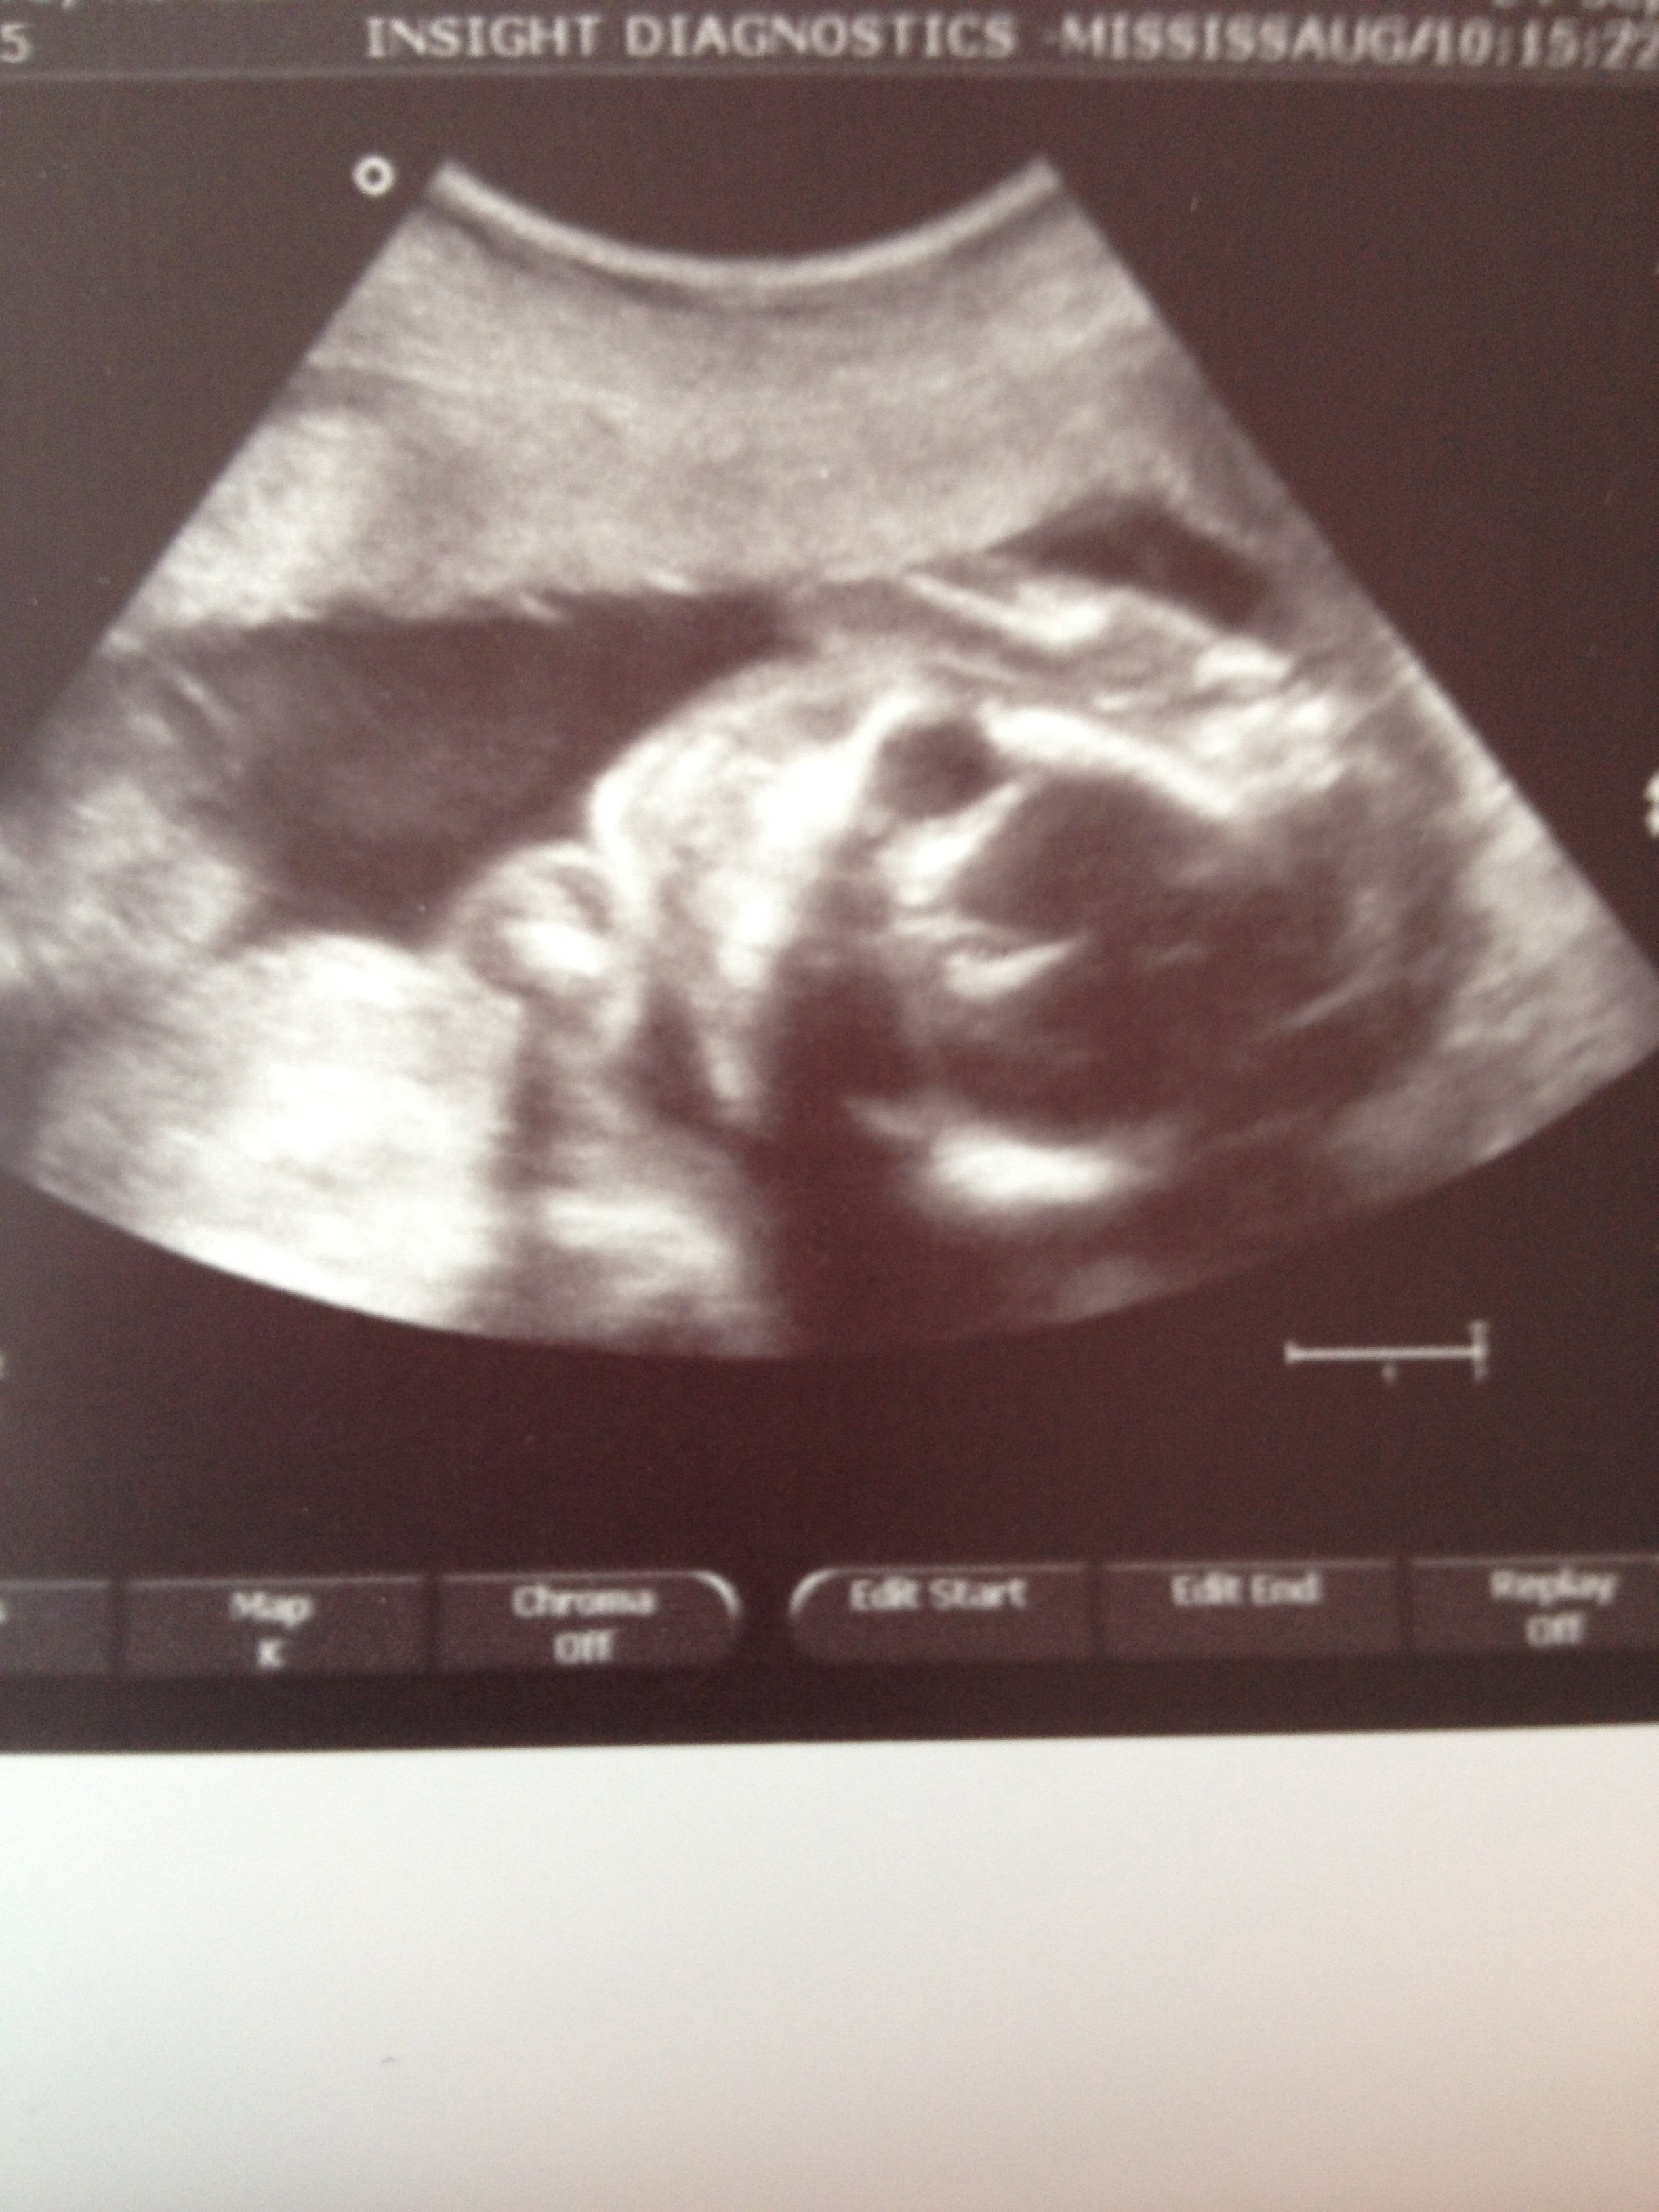

• Yesterday I had to go for a f/u u/s to my a/s for pictures of the heart. Baby was very cooperative this time. At the end the tech was showing me the screen and then said 'oh that's a great shot of the face' and printed a pic. Problem was the baby had moved already...

image

I had to laugh bc the pic was nothing like the amazing image on the screen before the baby moved.

Bonus points if you can tell if it's a girl or a boy!